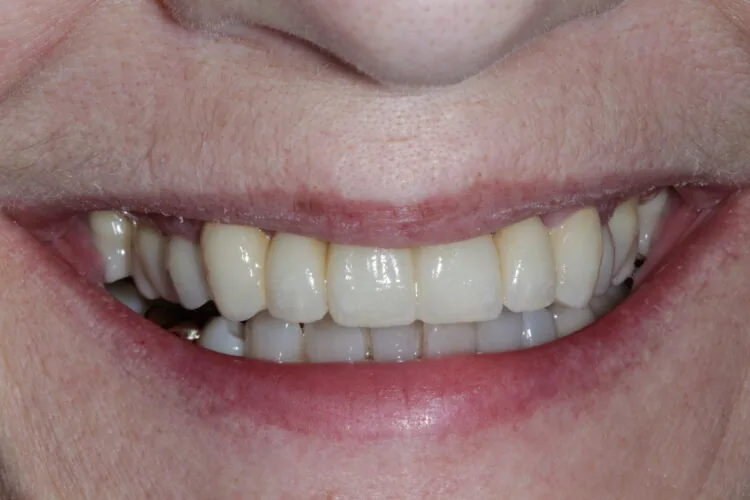

The final result delivered a dramatic transformation. The bridge and veneers blended naturally, restoring symmetry and confidence to the patient’s smile. Upon seeing the result for the first time, the patient was visibly emotional and described the outcome as far exceeding her expectations.

5. To complete the smile enhancement, porcelain veneers were placed on the premolars to increase the buccal corridor fill and broaden the smile.

4. After this phase, a definitive six-unit porcelain bridge was placed to restore aesthetics and function.